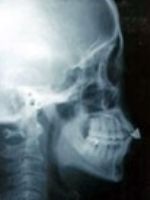

当院では、頭部側面レントゲン写真検査や内視鏡検査などにより、口やのどのどこに原因があるかを調べます。そして睡眠時無呼吸用のマウスピースにより治療効果が期待できるかどうかを診断します。

レントゲン検査